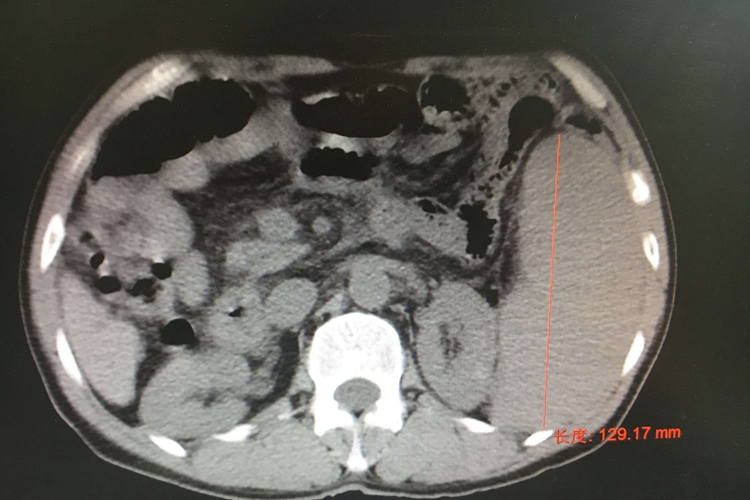

肝脾肿大

约90%患者出现脾大,少数患者肝大。